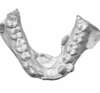

Important encombrement traité par gouttières

H-Intermédiaire 4